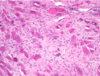

what type of tissue is this?

when this tissue is present, what is it indicative of?

what is it composed of mostly?

Granulation tissue

healing

proliferating capillaries